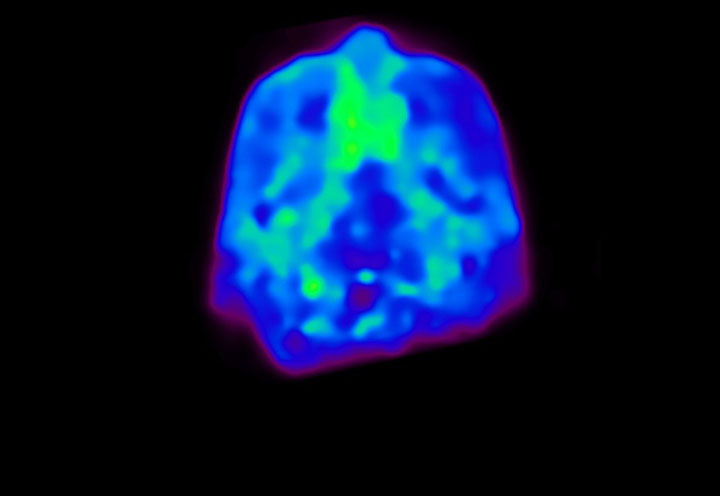

Head / Case4 : Amyloid

Coronal

Courtesy : Kindai University Hospital

- Imaging protocol

- Injected dose: 3.21 MBq/kg, 18F-Flutemetamol

- Uptake time: 100 minutes

- Scan time: 20 minutes